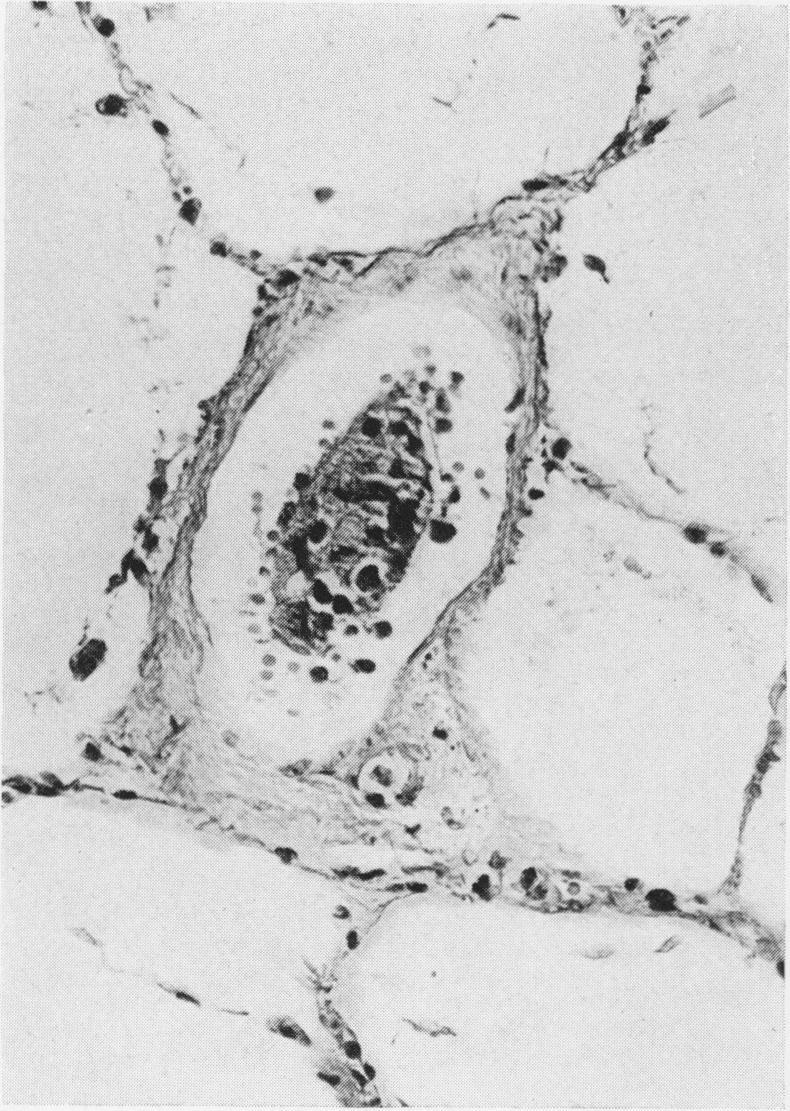

Detailed necropsies were performed on 26 individuals who had died of disseminated breast carcinoma, to assess the frequency of spread to the lungs, pleura and pericardium, and to determine the likely routes of spread to these sites. Tumour was present in the lung parenchyma in 67% of the lungs examined, in the visceral pleura in 75% and the parietal pleura in 50%. Although even small deposits of pleural tumour were invariably visible to naked-eye examination, lung parenchymal involvement was almost invariably microscopic, despite its frequently extensive distribution. This finding draws attention to the difficulties of clinical staging with respect to lung metastases. Tumour in lymphatics predominated over that in blood vessels in both lung and pleura and this, together with the widespread mediastinal lymphnode infiltration found, suggests that the lymphatic system forms the dominant route of spread of breast carcinoma to the thorax. The possible role of mediastinal lymphatics in the dissemination of breast cancer to bone and liver is also discussed. Our findings suggests that the fields of adjuvant irradiation after primary surgery should include the mediastinal lymphatic network.